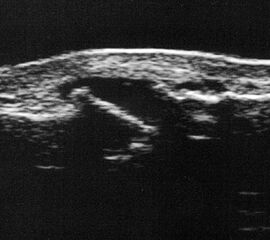

Fibulaverletzung beim Erwachsenen

Fibulafraktur mit Unterbrechung der Kortikalis und Hämatom.

Abbildung 13

Lagerung: Rückenlage, leichte Innrotation des Fußes.

Schnittebene: LS über distaler Fibula.

Referenzstruktur: Fibula im Längsverlauf.

Befunde: Bei einer Außenknöchelfraktur ist eine Unterbrechung der echogenen metaphysären Knochenlinie mit umgebendem flachen, echoarmen periostalen Hämatom zu sehen (Abb.13).

Cave: Ein Os subfibulare kann ebenfalls fälschlicherweise als Fibulaverletzung interpretiert werden!